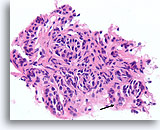

Afbeelding 20

Benigne, lymfocytische thyroïditis, schildklier FNA, celblok.

Deze afbeelding van de patiënt in afbeelding 19 toont een dicht lymfocytisch infiltraat met aangrenzende afgeplatte microfollikels met hurthlecelveranderingen.

20X

Afbeelding 20

Benigne, lymfocytische thyroïditis, schildklier FNA, celblok.

Deze afbeelding van de patiënt in afbeelding 19 toont een dicht lymfocytisch infiltraat met aangrenzende afgeplatte microfollikels met hurthlecelveranderingen.

20X